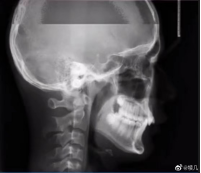

拍牙片時打了個哈欠,變成了毒液?用3D打印技術制作牙齒的好處

小編看到牙片表示:恐怖片果然來源于生活。有網友會問3D打印技術能制作牙齒嗎?小編告訴你:可以!那么用3D打印技術做牙齒有哪些好處呢?

3D打印首次用于牙科時,牙科實驗室主要是打印模型和手術導向器,而不是留在患者身上的產品。如今,3D打印技術正在利用增材制造來創造出持久且精確定制的優質產品,以滿足每位患者的需求。牙科3D打印技術由于研究機構和私營公司不斷發展,涵蓋了牙科的各個方面。3D打印一顆牙齒只要三分鐘,比傳統的制作方法快了十倍,而且3D打印的質量更高,因為該系統在繪制牙齒結構方面做的更好。